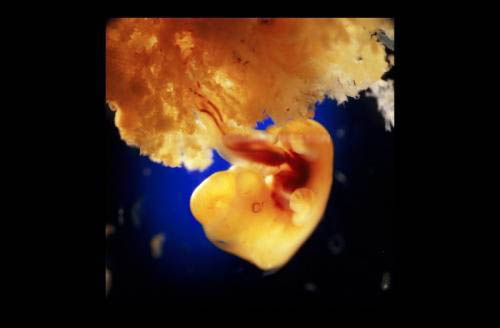

Предлагаю Вашему вниманию уникальный репортаж из женского тела.

Эти уникальные фотографии сделаны шведским фотографом Леннартом Нильсоном ещё в 1965 году. Сам фотограф родился в 1922 году и стал первым, кто при помощи специального оборудования и фотокамер, смог проникнуть внутрь женского тела и снять весь процесс зарождения новой жизни.

Первые фотографии эмбриона появились в печати ещё в 1953 году, и это событие вдохновило фотохудожника на создание новых работ.

Для того, чтобы показать развитие человека с самого начала, он поместил микрокамеру и микроосветитель на конец трубки цистоскопа, которым осматривают мочевой пузырь, и снял свои уникальные фотографии прямо оттуда, откуда люди делают первый шаг в мир...

Вот она - наша история зарождения жизни!